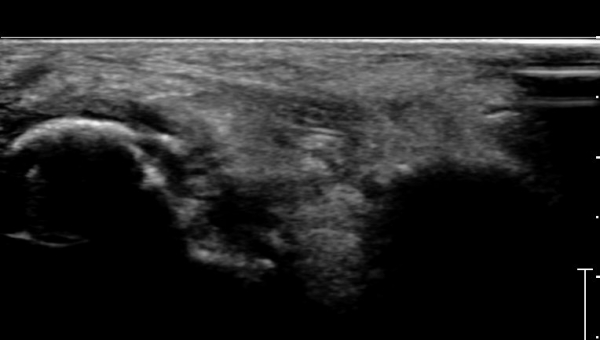

ÃÊÀ½ÆÄ°Ë»ç :  Àü°ÅºñÀδë Á¾´Ü¸é°Ë»ç¿¡¼­ Àü°ÅºñÀδëÀÇ Àú¿¡ÄÚ À§ÃàÀÌ °üÂûµÇ°í °Å°ñ °æºÎÀÇ °ß¿­°ñÀý ¹×

°Å°ñÁÖ»ó°ñ°üÀý ºÎÁ¾ÀÌ °üÂûµÈ´Ù(»çÁø 1).